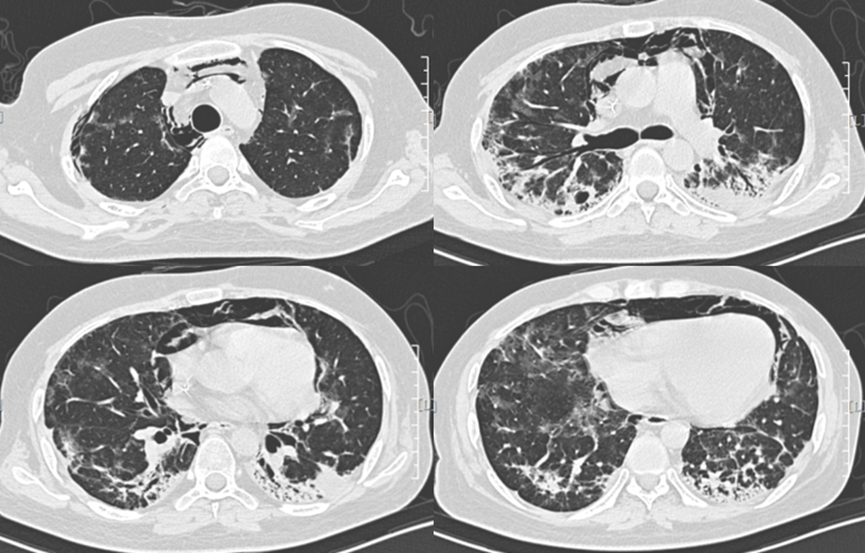

9月28日复查胸部CT:双肺磨玻璃渗出及双下肺实变病灶均好转,可见胸膜下间质增生(图4)。其间一直口服伏立康唑抗真菌预防用药。治疗过程中,患者血象低,给予升血细胞、输血、输注丙种球蛋白及白蛋白等对症支持治疗。总疗程为2个月。

图片

图4  患者胸部CT(2018年9月28日)